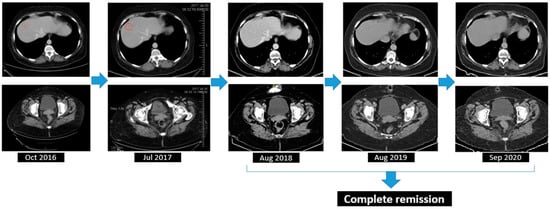

2.2.6. Follow-Up